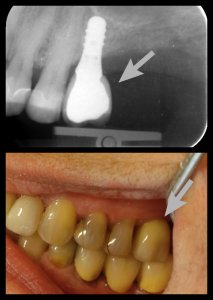

ΠΕΡΙΣΤΑΤΙΚΑ ΜΕ ΤΟΠΟΘΕΤΗΣΗ ΕΝΔΟΟΣΤΙΚΩΝ ΕΜΦΥΤΕΥΜΑΤΩΝ. ΌΠΟΥ ΧΡΕΙΑΣΤΗΚΕ ΠΡΑΓΜΑΤΟΠΟΙΗΘΗΚΕ ΑΝΑΠΛΑΣΗ ΟΣΤΟΥ ΚΑΙ ΟΥΛΙΚΩΝ ΕΛΕΙΜΜΑΤΩΝ ΜΕ ΧΡΗΣΗ ΜΟΣΧΕΥΜΑΤΩΝ ΚΑΙ PRF